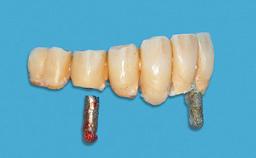

Mandibular Overdenture Supported by a CAD/CAM-milled Bar with Long Distal Extensions on Two Conventionally Loaded Implants

Defining Characteristics Fully edentulous lower jaw to be rehabilitated with an implant-borne removable overdenture